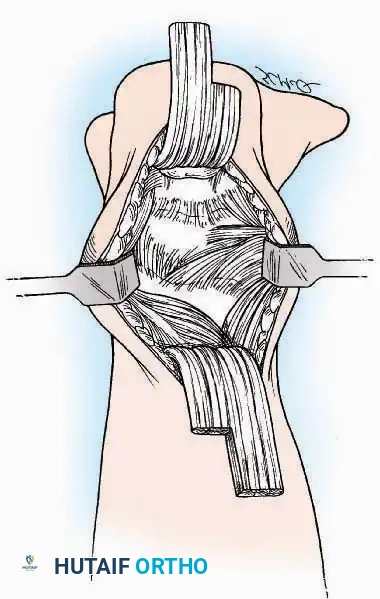

Approaches to the Metatarsophalangeal (MTP) Joint of the Great Toe

The first MTP joint is the epicenter of forefoot reconstructive surgery. Exposure can be achieved via medial or dorsomedial trajectories.

Medial Approach

Indications: Hallux valgus correction (bunionectomy), first MTP arthrodesis, or cheilectomy.

Surgical Technique:

* Incision: Make a curved incision 5 cm long on the medial aspect of the joint. Begin just proximal to the IP joint, curve it over the dorsum of the MTP joint (medial to the extensor hallucis longus [EHL] tendon), and terminate on the medial aspect of the first metatarsal 2.5 cm proximal to the joint.

* Superficial Dissection: As the deep fascia is incised, identify and laterally retract the medial branch of the first dorsal metatarsal artery and the medial branch of the dorsomedial nerve (a terminal branch of the superficial peroneal nerve).

* Deep Dissection: Dissect the fascia from the dorsum down to the bursa overlying the medial eminence of the metatarsal head.

* Capsulotomy: Make a curved incision through the bursa and joint capsule. Begin dorsomedially, continue proximally dorsal to the metatarsal head, sweep plantarward, and end distally on the medioplantar aspect of the joint. This creates an elliptical, racquet-shaped flap attached at the base of the proximal phalanx.

⚠️ Surgical Pitfall

While distal reflection of this racquet flap provides ample exposure of the first MTP joint, the extensive subfascial undermining required can compromise the vascularity of the skin flap, leading to delayed healing or necrosis. Consequently, the dorsomedial approach is often preferred in modern practice.

Dorsomedial Approach

Indications: Preferred approach for primary and revision first MTP arthroplasty, arthrodesis, and complex bunion corrections due to superior angiosome preservation.

Surgical Technique:

* Incision: Begin just proximal to the IP joint and extend proximally for 5 cm, running parallel and strictly medial to the EHL tendon.

* Exposure: Divide the superficial fascia. Identify and retract the EHL tendon laterally.

* Capsulotomy: The capsule can be incised longitudinally in the exact plane of the skin incision, allowing for subperiosteal elevation of the capsule medially and laterally, preserving the vascular supply to the medial skin flap.